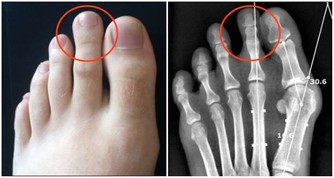

血尿:最常見一種,泌尿道任何部位有損傷出血均可引起血尿,比如急性腎炎、泌尿道結石、結核、腫瘤、泌尿系統的先天畸形或運動性血尿等。